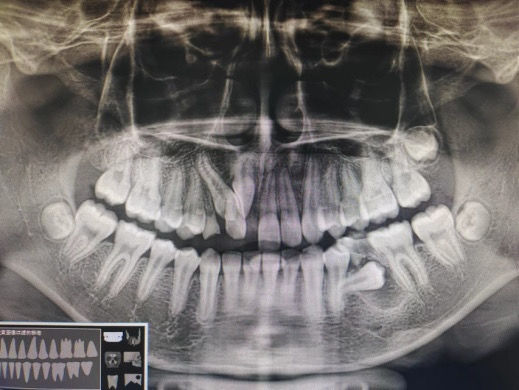

据了解,这位患者在一个月前便因牙列不齐的问题,在家长的陪同下来到了南顺城医院口腔科就诊。经过口腔科的仔细检查,并结合CBCT影像技术,发现患者不仅存在牙列问题,更在其左下后牙位置长有一处含牙囊肿。因囊肿的范围较大,且涉及到一颗完全埋伏阻生的变异恒牙,其牙根还呈现弯曲状态,给手术带来了一定难度。

南顺城医院口腔科充分讨论了手术方案,在局部麻醉下为患者进行了微创手术,不仅成功摘除了含牙囊肿,还一并将因囊肿影响而无法保留的恒牙和上方未脱落的乳牙拔除。

含牙囊肿是牙齿未能正常萌发引起的囊肿,好发于10岁到30岁。一般来说小的含牙囊肿无明显临床症状,大的囊肿会导致颌骨膨胀及相邻牙的移位。含牙囊肿常通过手术进行治疗,将囊肿和累及的牙齿一并摘除,解除对周围组织的影响。